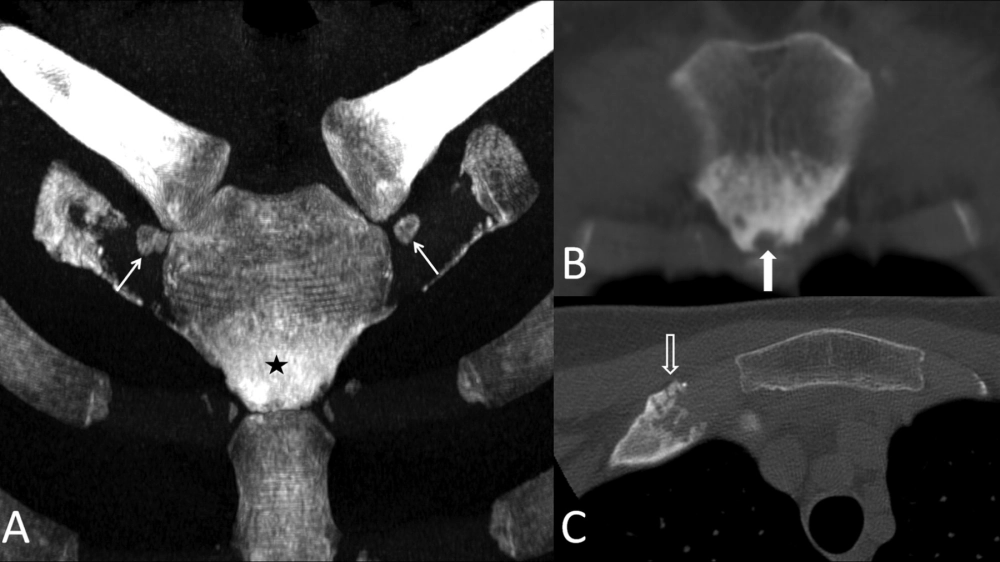

X-quang cho thấy sự biến dạng của bệnh Paget xương